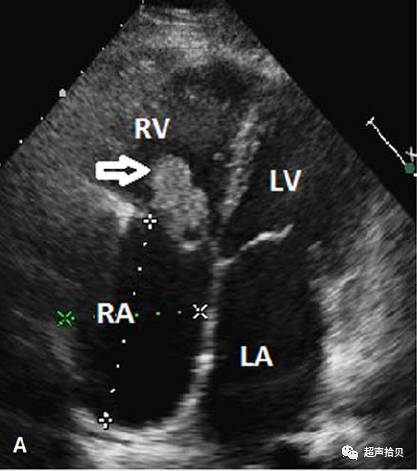

50岁的妇女,因间歇性寒颤及发烧在心脏外科接受治疗1个月;2年前,曾行房间隔缺损及三尖瓣成形修复术,三尖瓣为32号爱德华兹成(EdwardsLifesciences,尔湾,CA)体检:37.48c体温,98 /分心率,血压140/100毫米汞柱,不规则的心脏节律,并在瓣膜听诊区无病理性杂音。经胸超声心动图显示右心室一个带蒂移动肿块(30 3 23毫米),源自三尖瓣环附近后隔三尖瓣后隔,通过三尖瓣口室环,脱入右心房(图1A和视频1)。这一肿块导致舒张功能性三尖瓣狭窄(图1B和录像2)。左心房和右心房增大。心电图显示房颤。

图1.病例1.

A,经胸超声心动图显示三尖瓣瓣膜环的肿块(箭头表示粘液瘤)。

RV,右心室; RA,右心房; LV,左心室; LA,左心房; AV,主动脉瓣。